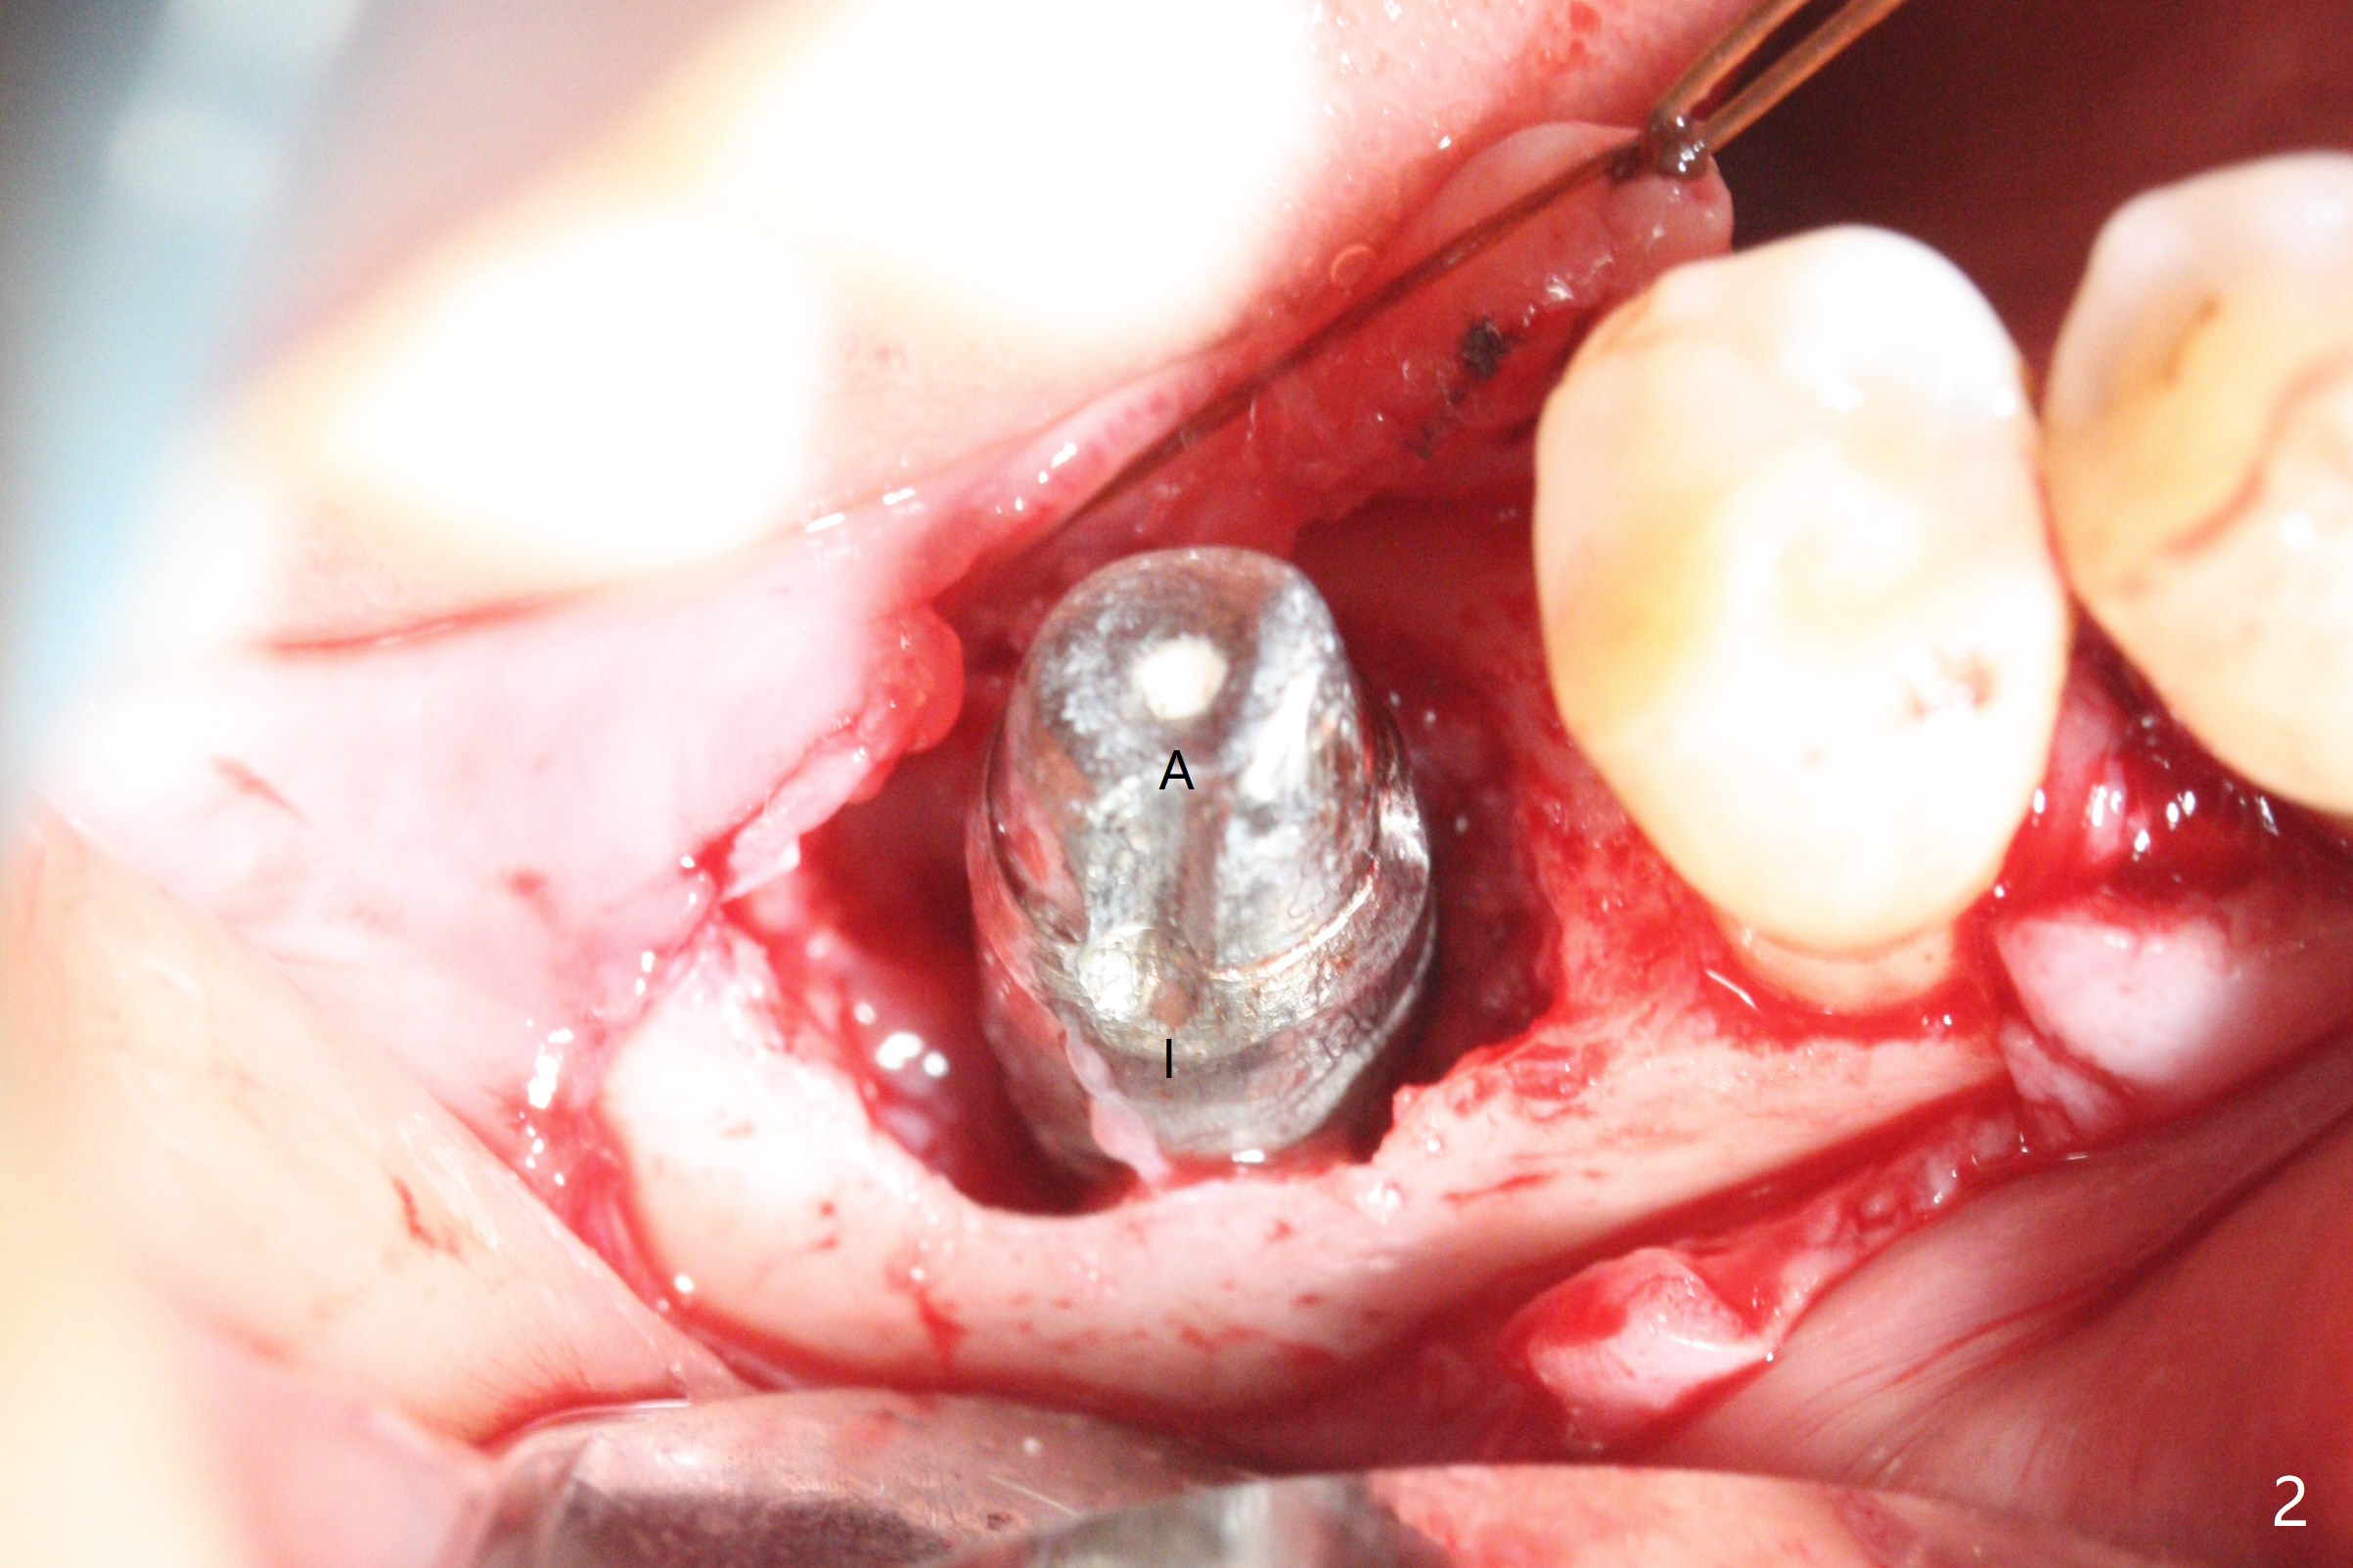

There are signs of periimplantitis at #30 eleven months postop (Fig.1 (* bone loss)). The bony defect (Fig.2) will be filled with allograft mixed PRF liquid to form sticky bone (Fig.3,4), followed by PRF membrane (not shown) and a piece of 6-month membrane (Fig.5). A hole is cut so that the 6-month membrane can slide down the abutment (Fig.2,5 A) to cover the bone graft around the implant (Fig.2,7 I). Setting acrylic is applied around the abutment and neighboring teeth for further protection and holding (Fig.8). The periimplantitis does not resolve nearly 7 months post graft. The implant will be removed. Prepare UF extra wide kit and try to insert 6.5 or 7.0 mm tap. Also prepare sticky bone and Cytoplast for wound closure. Implant removal involves surgical handpiece, 6.2/7 mm trephine bur, elevators, and implant driver. The defect is large (Fig.9) with the low buccal crest (Fig.10) and bone graft with PRF ("sticky bone") is placed, covered by PRF and 6-months membrane (Fig.11). The next implant will be placed with guide. If oral hygiene is not ideal, choose a bone level implant. The middle of the wound dehiscences slightly 8 days postop (Fig.12), accounting for mild loss of bone graft 1 year postop (Fig.14). The keratinized gingiva is apparently wide 1 year postop (Fig.13). There is mild loss of bone graft in the middle of the superficial area (Fig.14). The buccal plate seems to regenerate 1 year postop (pandemic delay, Fig.15).